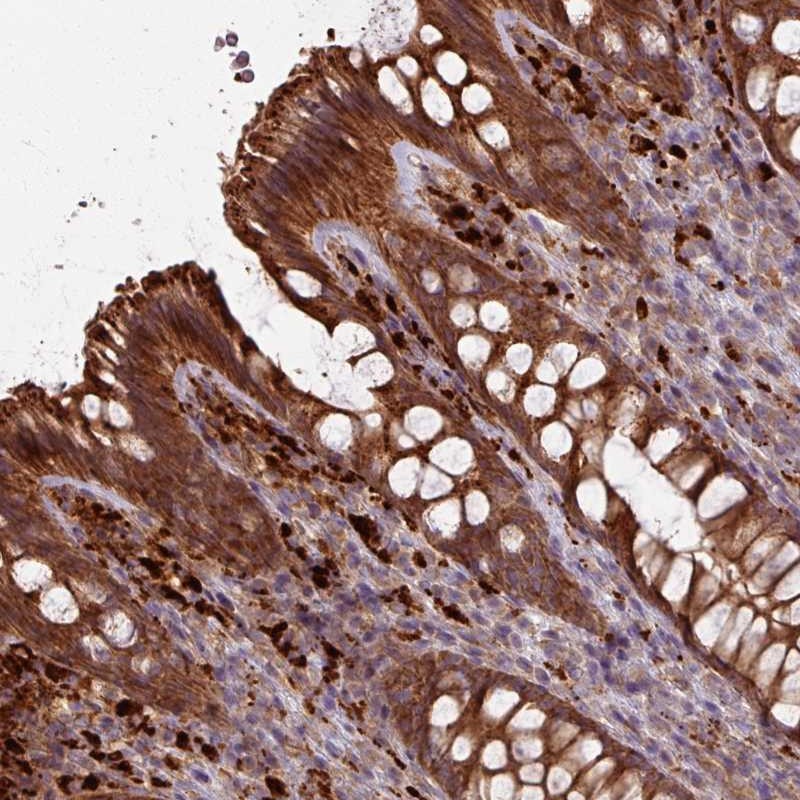

Immunohistochemical staining of human colon shows strong cytoplasmic positivity in glandular cells.